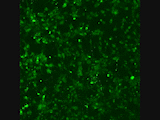

- 2p microscopy

- Automated Live-cell fluorescence microscopy